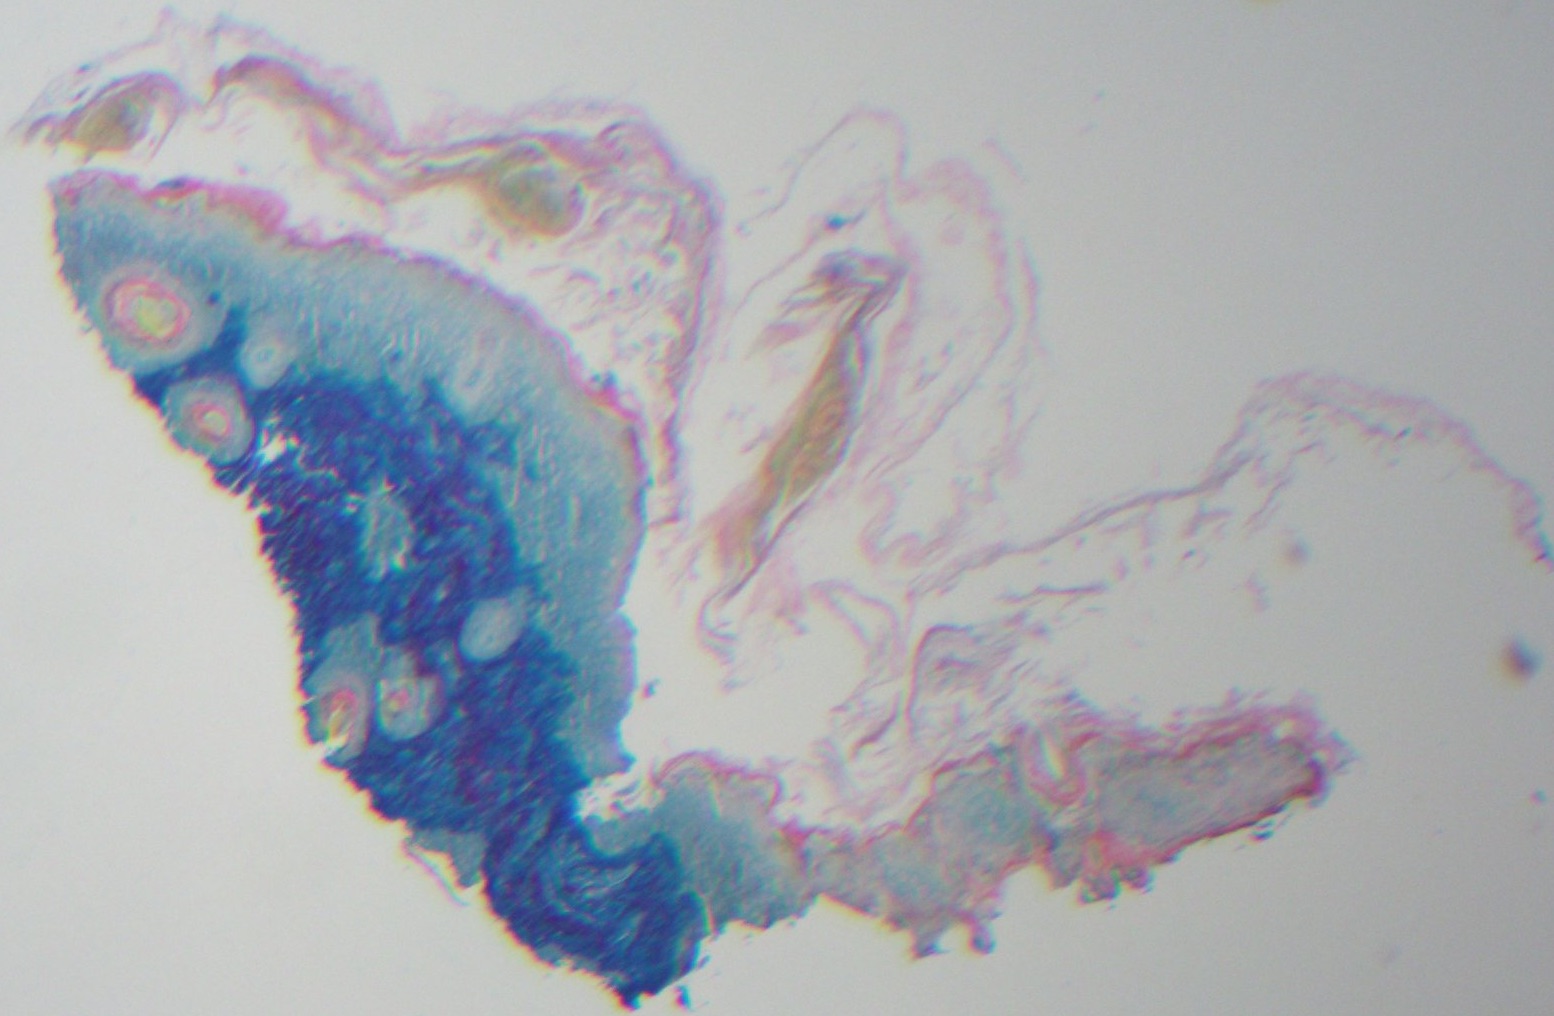

Diagnostic tests. A punch biopsy was done of one of the scalp lesions and was stained with hematoxylin and eosin (Figure 3) as well as with colloidal iron (Figure 4). The biopsy revealed atrophic epidermis and interface dermatitis with positive staining for mucin, findings suggesting a diagnosis of neonatal lupus erythematosus (NLE). Results of a complete blood cell count and electrocardiography were normal.

Figure 4. Colloidal iron stain results of a biopsy specimen.